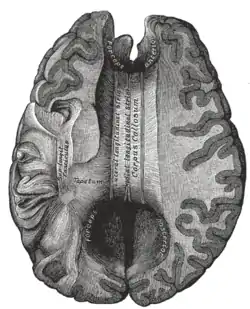

- In some children without “classic” holoprosencephaly, microforms of holoprosencephaly may be noted on MRI, including missing olfactory tracts and bulbs and absent or hypoplastic corpus callosum.

TCF4 – In 2007, deletions of or point mutations in this gene, which is located on 18q, were identified as the cause of Pitt-Hopkins disease. This is the first gene that has been definitively shown to directly cause a clinical phenotype when deleted. If a deletion includes the TCF4 gene (located at 52,889,562-52,946,887), features of Pitt-Hopkins may be present, including abnormal corpus callosum; short neck; small penis; accessory and wide-spaced nipples; broad or clubbed fingers; and sacral dimple. Those with deletions inclusive of TCF4 have a significantly more severe cognitive phenotype.